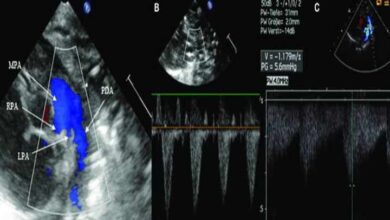

مجرای شریانی باز (PDA) چیست؛ علایم و درمان مجرای شریانی باز

مجرای شریانی باز (PDA) چیست؟ بیماری مجرای شریانی باز یک بیماری قلبی است که عموماً در هفتهها یا ماههای اولیه…